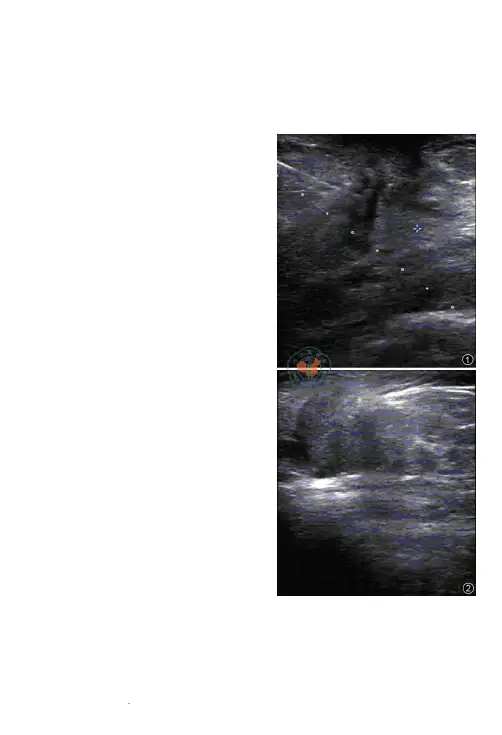

介入超声影像学介入性超声在乳腺结节穿刺活检中的应用体会张义连 李苗 DOI:10.3877/cma.j.issn.1672-6448.2013.02.018作者单位:725000 陕西省安康市中心医院功能科 超声检查能较清晰地显示乳腺结节病变。

超声引导下穿刺乳腺结节可实时显示针道及进针的全过程。

尤其对扪诊不清、位置较深、紧邻胸大肌的乳腺结节,可通过超声引导穿刺活检,该方法取材成功率高,临床上收到非常好的效果[1]。

本院于2007年1月至2011年6月对121例超声提示乳腺结节患者采用超声引导穿刺活检,取得良好的效果,现将结果报道如下。

常规器械消毒,患者充分暴露受检部位,经超声穿刺引导线引导下探头置于乳腺结节处初步确定最佳穿刺部位、路径及方式(图1,2)。